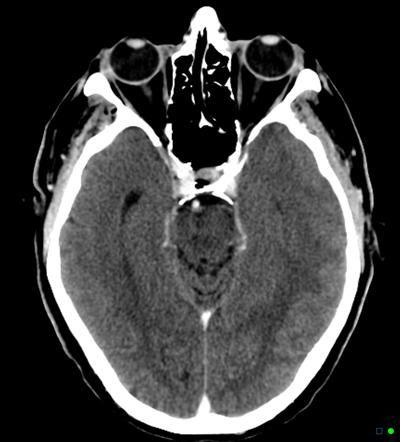

相关图片